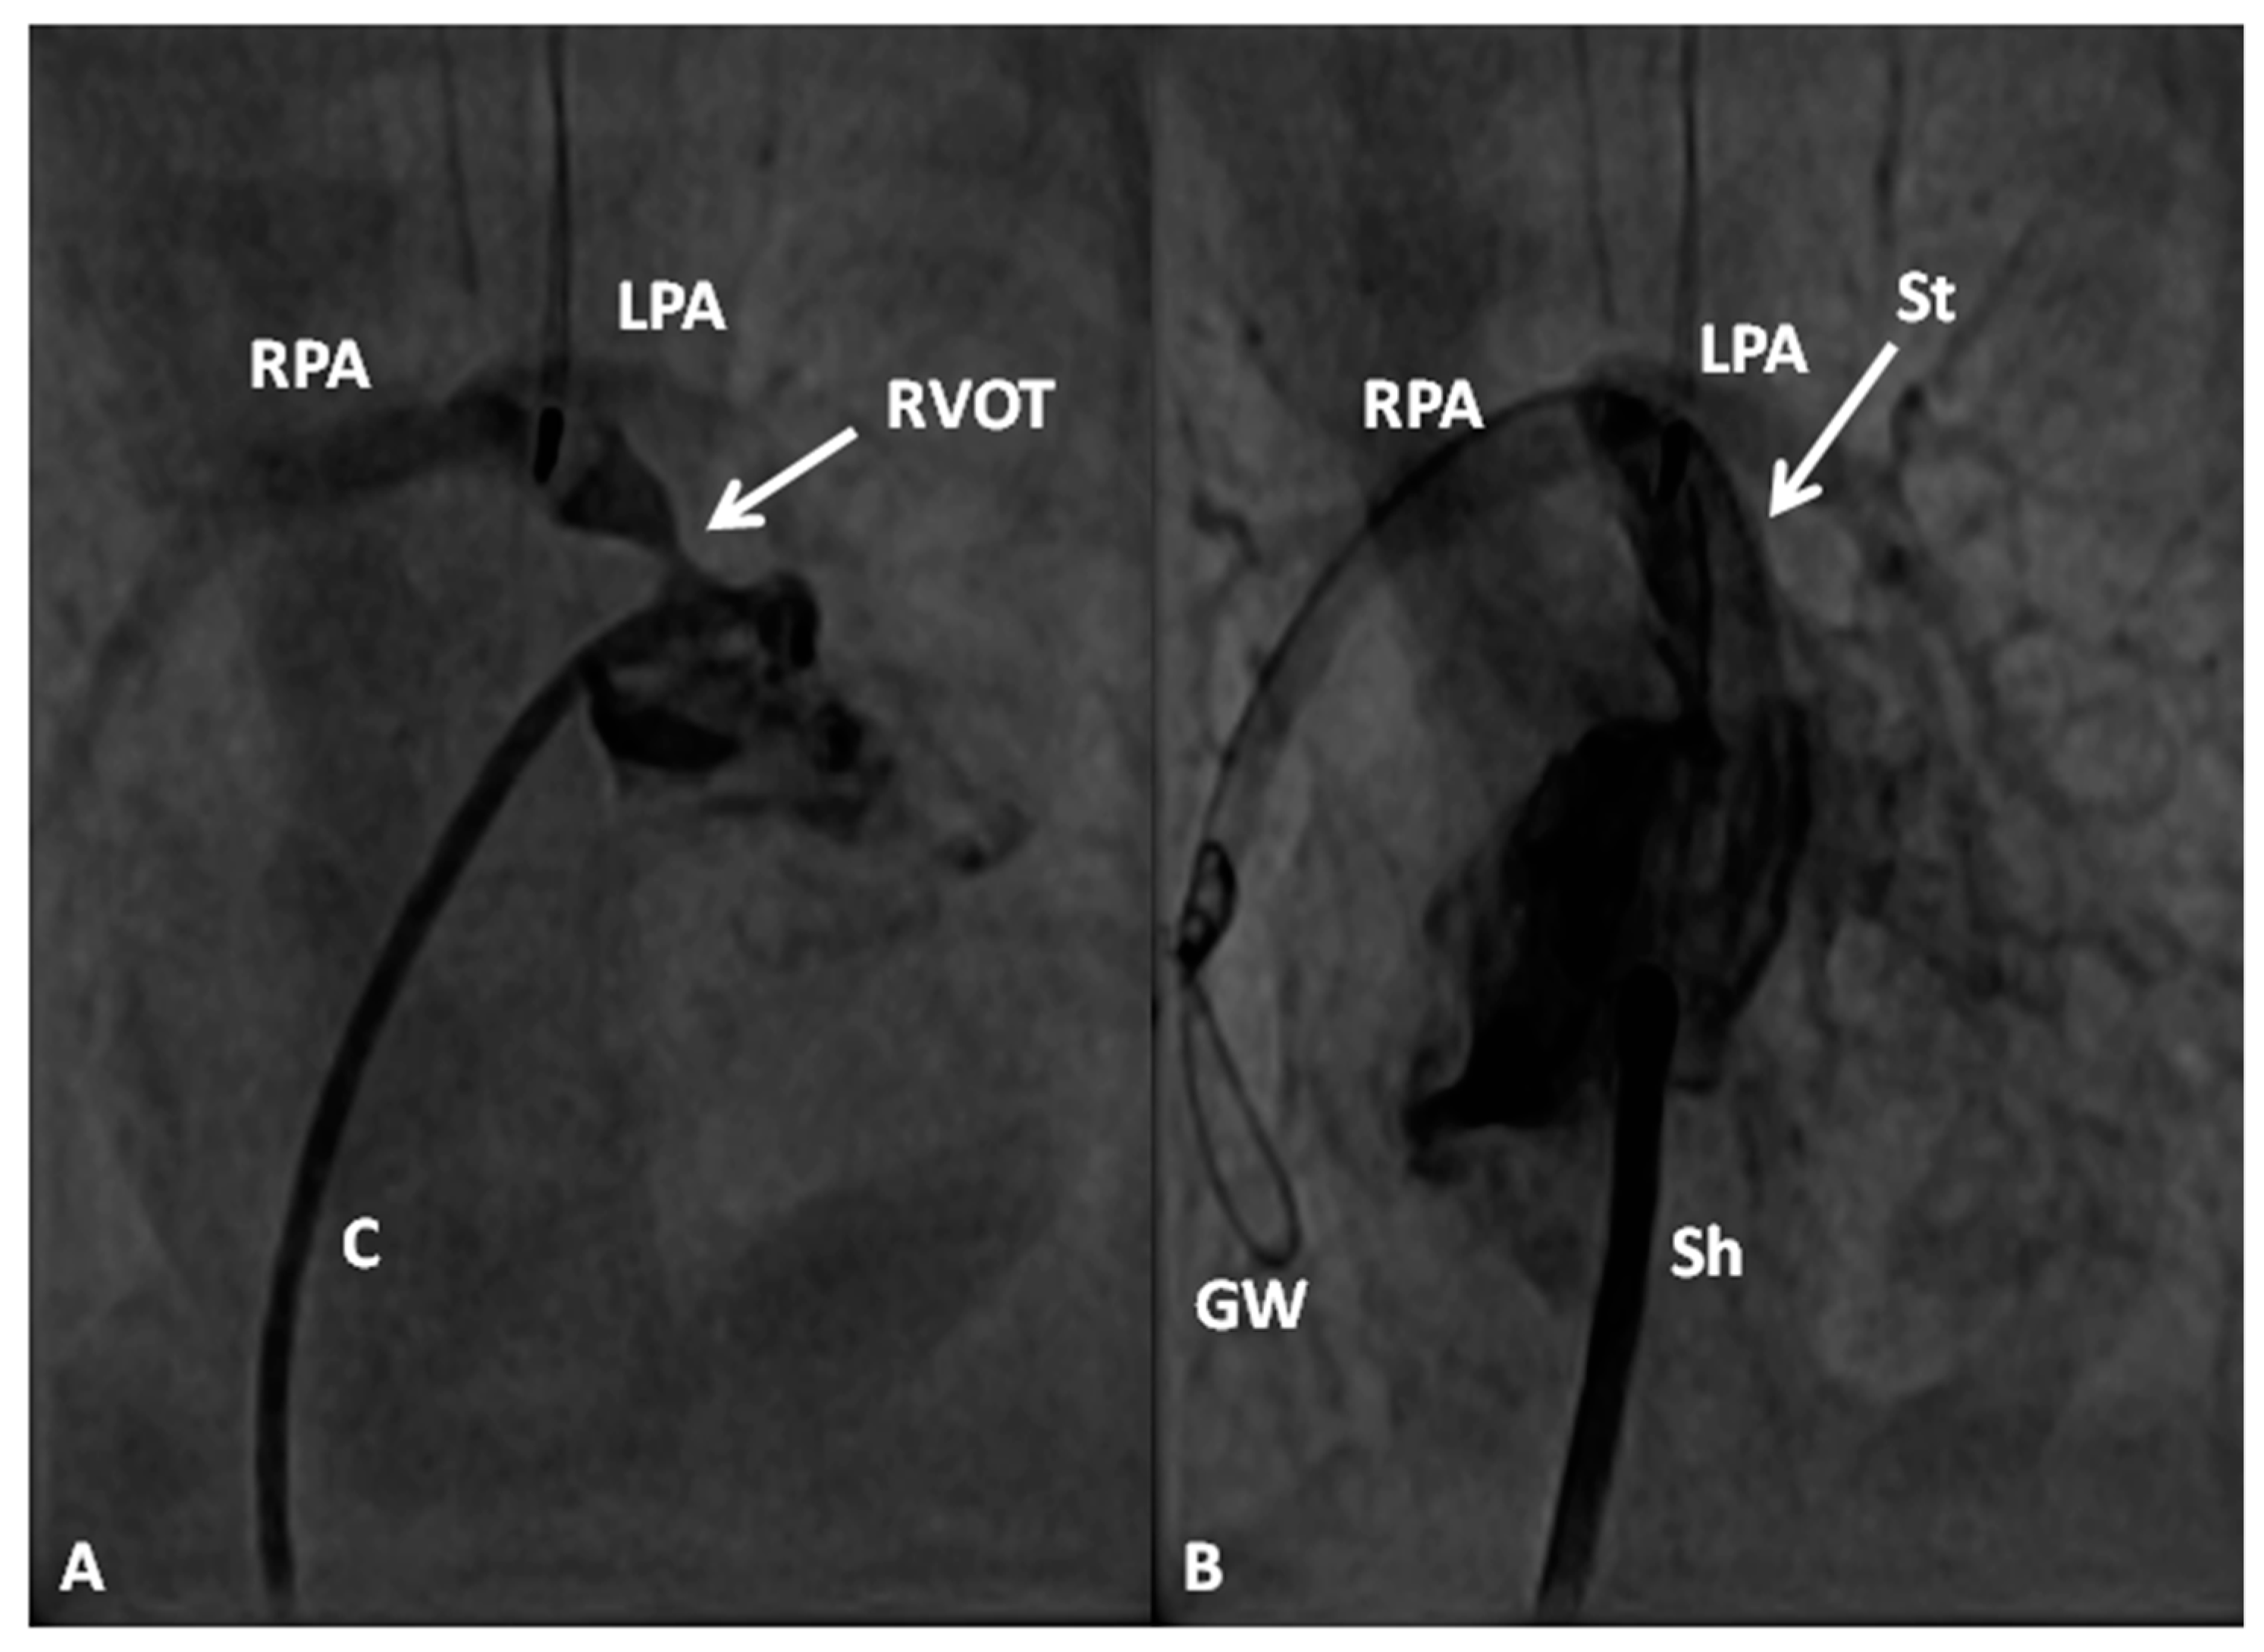

At the time of presentation, usually in the early infancy, palliation depending the physiological abnormality (modified BT shunt or pulmonary artery banding) (Figure 7) is performed after initial stabilization.

The pathophysiology produced by multiple defects in the above two entities is similar to that described for tricuspid atresia and consequently the management is similar [7,120,121]. The general objective is to accomplish Fontan circulation by staged total cavopulmonary connection. In young babies with decreased pulmonary blood flow, a modified Blalock–Taussig shunt (Figure 7A) is performed and if the pulmonary blood flow is increased, PA banding (Figure 7B) is undertaken. Relief of aortic coarctation, if present, should be provided. Subsequently, bidirectional Glenn (Figure 8 and Figure 9) and Fontan completion (Figure 10 and Figure 11) are undertaken as described in the “Tricuspid Atresia” section. Similarly, subaortic obstruction should be addressed by bypassing the obstruction by Damus–Kaye–Stansel, again as described in the “Tricuspid Atresia” section.